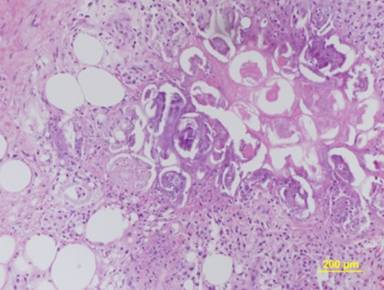

In November 2009, after a second episode of acute pancreatitis, the patient was referred to our department. Laboratory investigations showed a hemoglobin concentration of 8.3 g/dL (reference range: 14.0-17.5 g/dL), amylase of 113 U/L (reference range: 0-53 U/L) and lipase of 1,508 U/L (reference range: 0-60 U/L). CEA, CA 19-9 and alpha-fetoprotein were within the normal range. Upper digestive endoscopy confirmed the presence of an ulcerated mass infiltrating the second duodenal portion, with evidence of recent bleeding. The endoscopic biopsy of the mass was positive for adenocarcinoma (grade 2-3) of pancreatic origin with widespread necrotic areas. A biopsy of the subcutaneous nodule confirmed the presence of areas of necrotic subcutaneous fat surrounded by chronic inflammation consistent with pancreatic panniculitis (Figure 3).

|

Figure 3. Skin biopsy, lower leg: lobular fat necrosis with characteristic “ghost cells” and a mixed inflammatory infiltrate at the margin of saponification (H&E). |